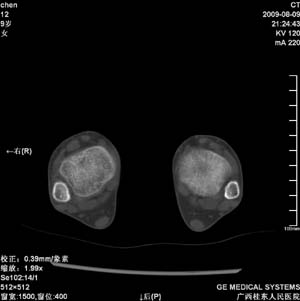

标题: PED2867:右侧内踝肿胀,骨质改变,请各位老师会诊 [打印本页]

标题: PED2867:右侧内踝肿胀,骨质改变,请各位老师会诊

九岁小朋友,近期左侧内踝疼痛,局部肿胀,平时无特殊,近期经常溜干冰

对不起,是右侧内踝肿胀

左侧内踝密度增高,请结合临床!